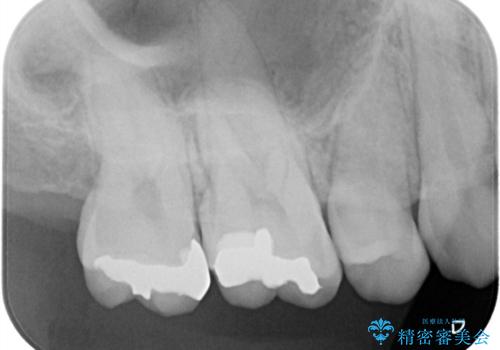

- 金属を外してセラミックを入れたいことを主訴に来院された患者さんです。

セラミックインレーにて修復を行いました。